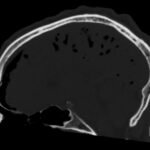

Tension pneumocephalus is a rare neurosurgical emergency requiring cranial decompression to prevent permanent neurological injury, herniation, and death. In this report, we present a trauma patient struck by a knife in the forehead who presented with agitation and vomiting. Imaging ultimately revealed a minimally displaced frontal sinus fracture through both the anterior and posterior walls of the sinus. This disruption, acting as a ball-valve for air entry into the cranium, resulted in extensive pneumocephalus and eventual tension physiology. The patient required immediate neurosurgical decompression. This case illustrates both the importance in recognition of this uncommon pathology as well as the need for rapid reassessment with clinical changes in trauma patients.